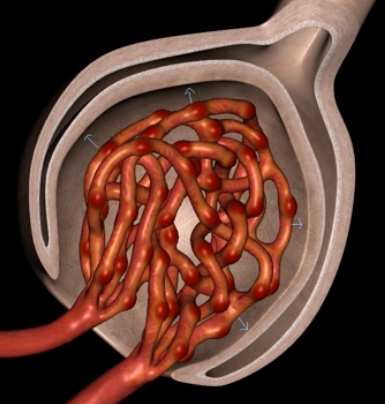

Podocytes

nephron

type of cell

Bowman’s capsule

Glomerular filtration involves pressured movement of fluid and solutes from the blood into ___ (blue arrows)

capillaries

orange

green

endothelium

filtration membrane is composed of ____ (yellow)

visceral layer of Bowman’s capsule

purple

basement membrane

blue

afferent arteriole

visceral layer

orange cells

foot processes

filtration slits/slit diaphrams

yellow

capsular space

outlined in blue

blue space